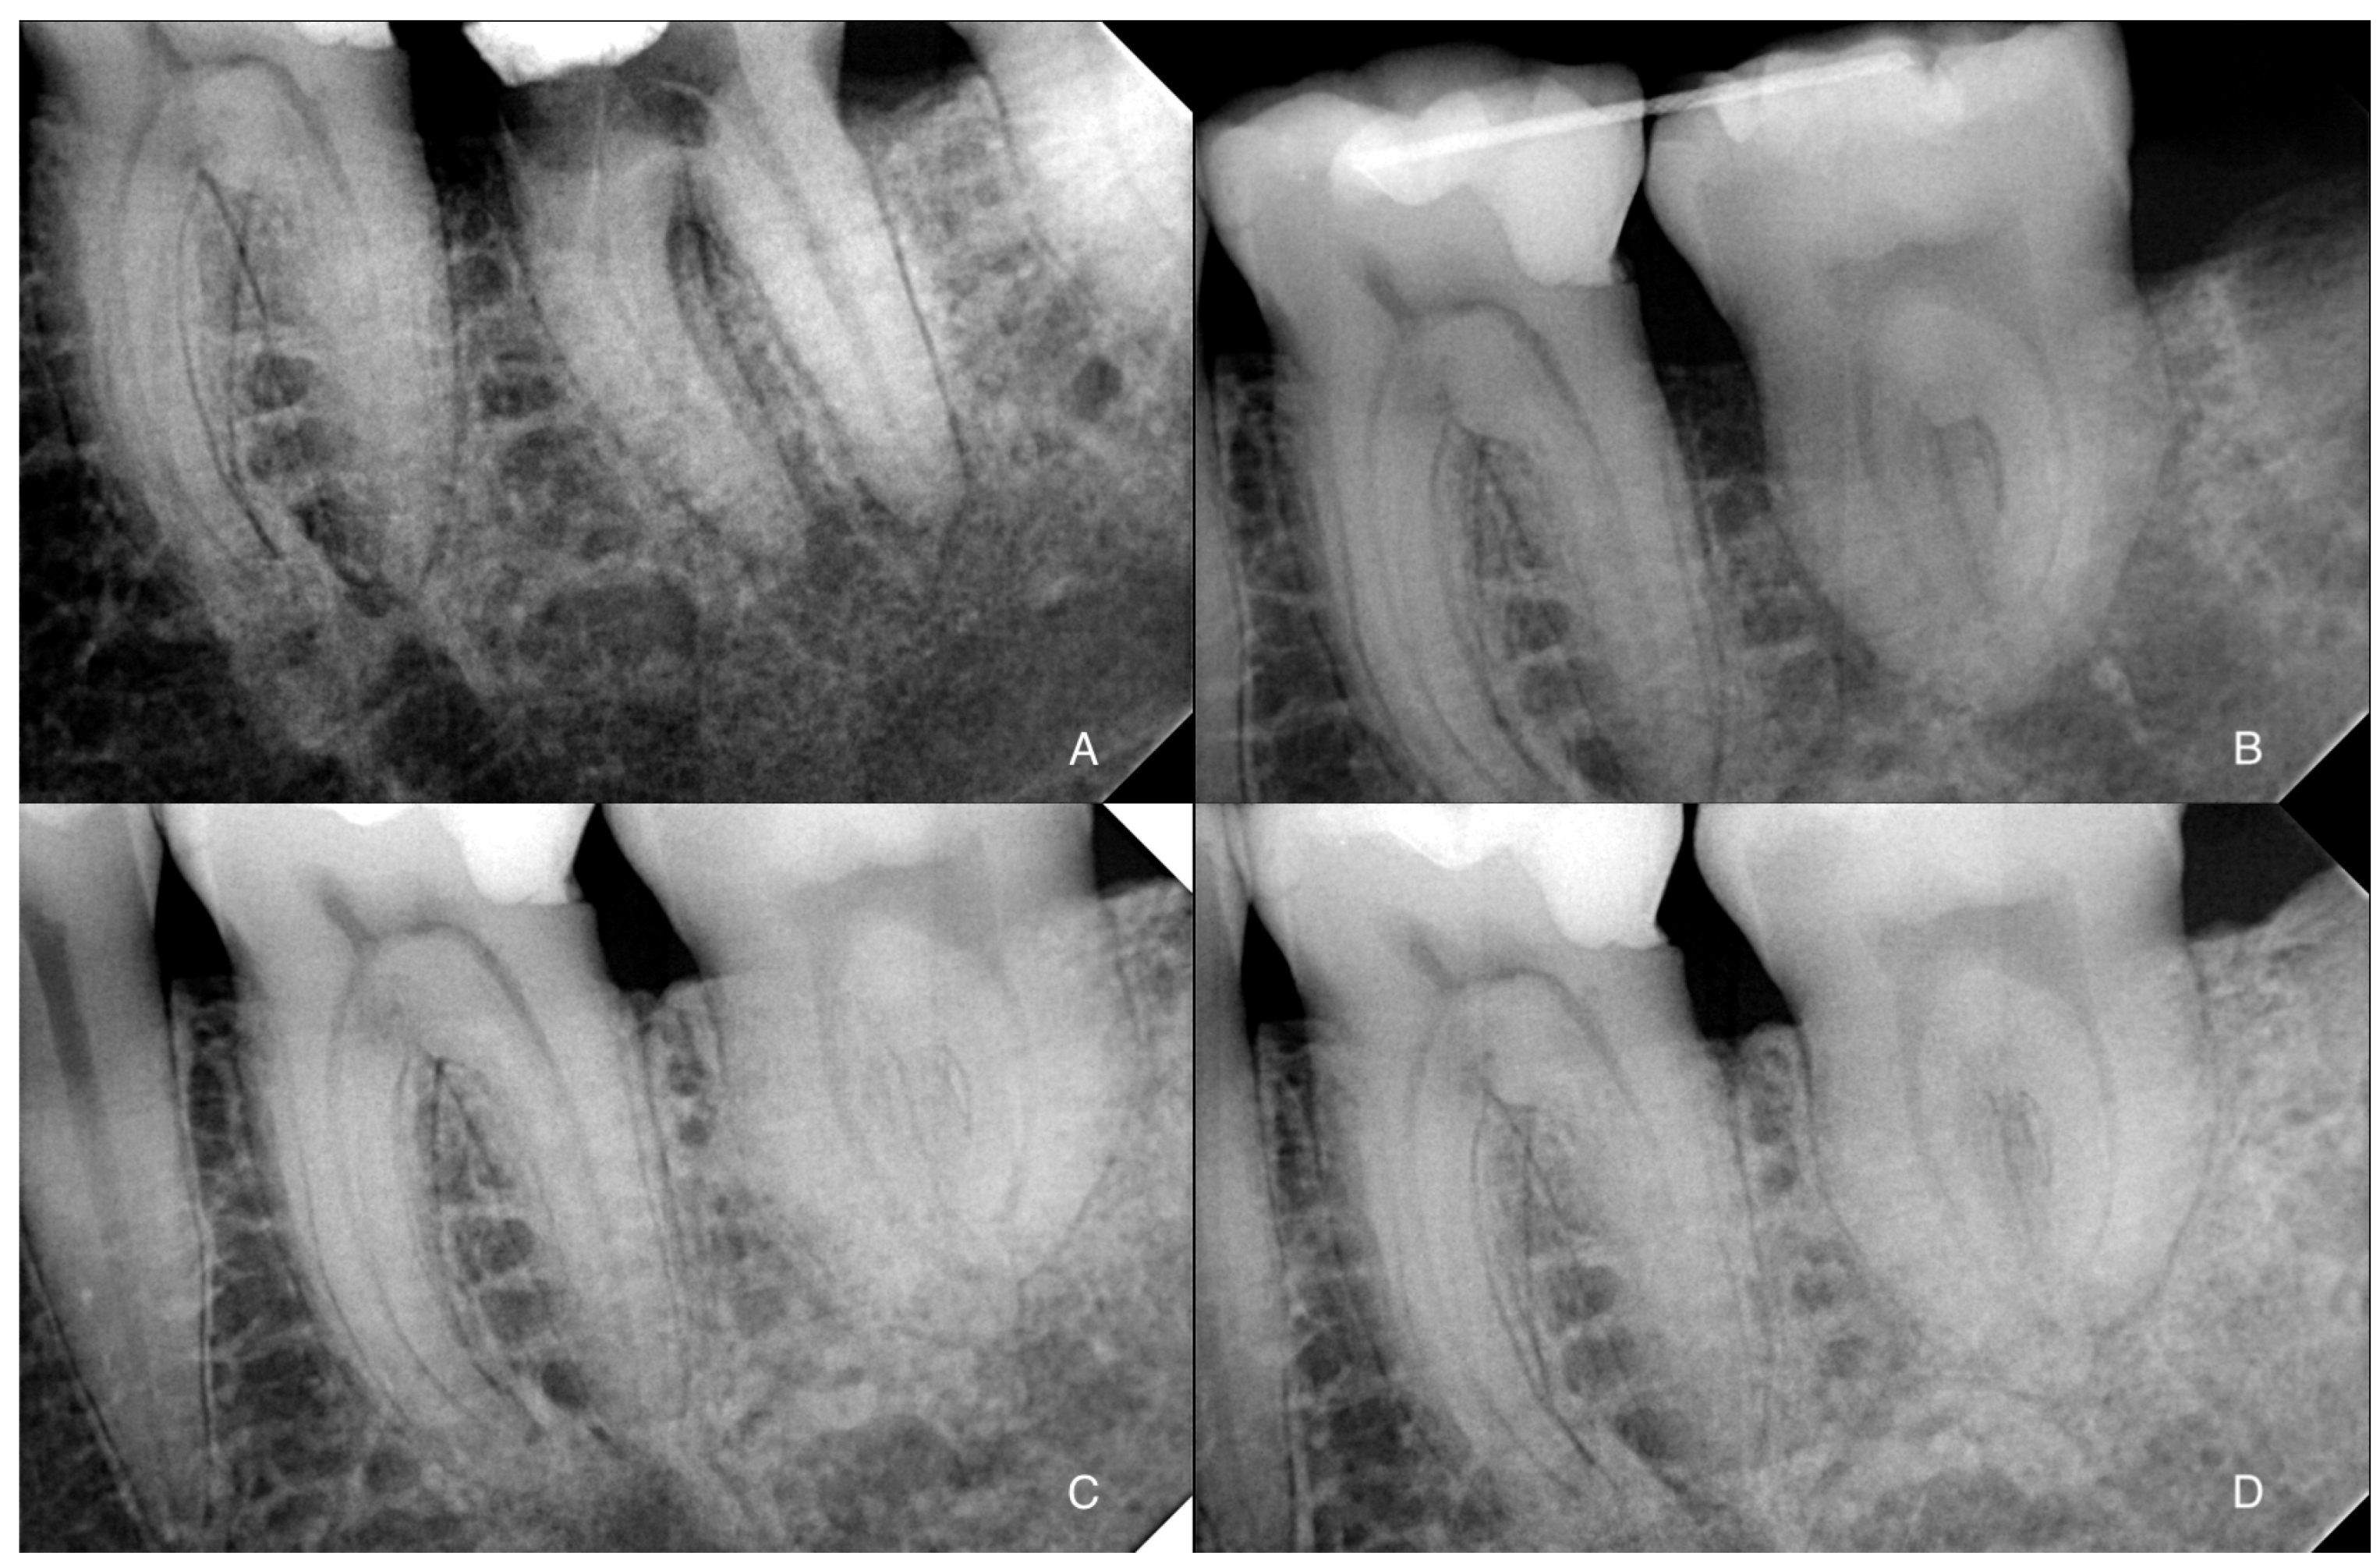

After two weeks, the sutures and the splint were removed according to International Association for Dental Traumatology (IADT) treatment guidelines for avulsed permanent teeth replanted immediately [10]. The tooth had mobility but presented a physiological probing. In mature transplanted teeth, root canal treatment is performed 2 to 12 weeks after transplantation; on the contrary, immature transplanted teeth are monitored following the decisional algorithm shown in Figure 3.

Figure 3. Decisional algorithm for the endodontic management of transplanted teeth.